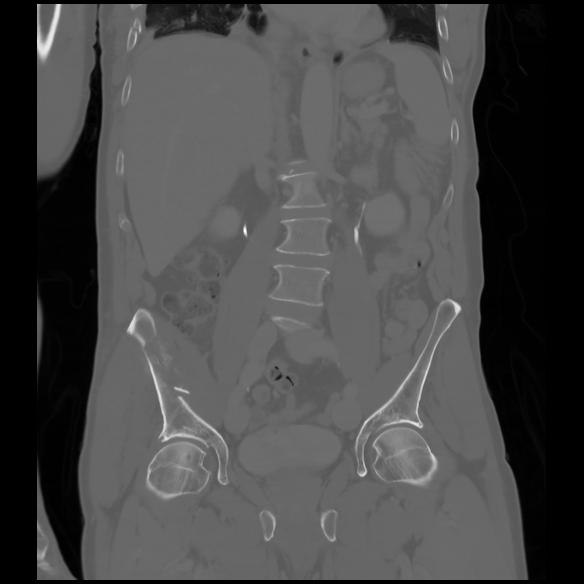

6 CUERPO,CE,Coronal,3.000,CUERPO,Coronal,